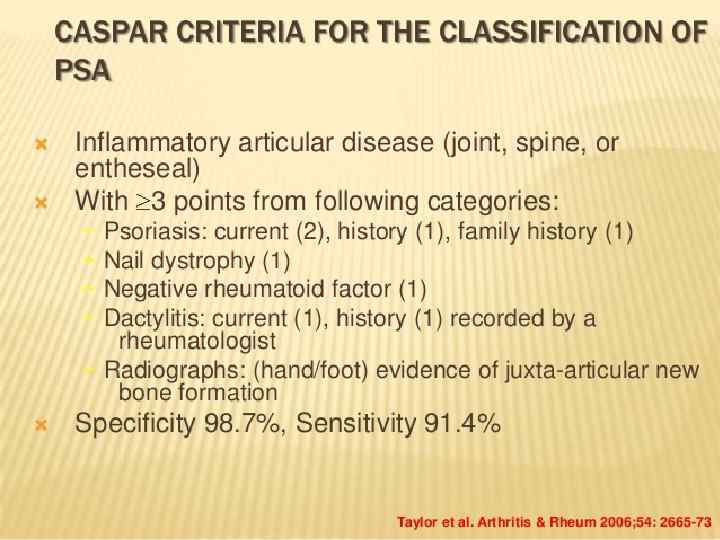

Psoriatic arthropathy

Psoriatic arthropathy